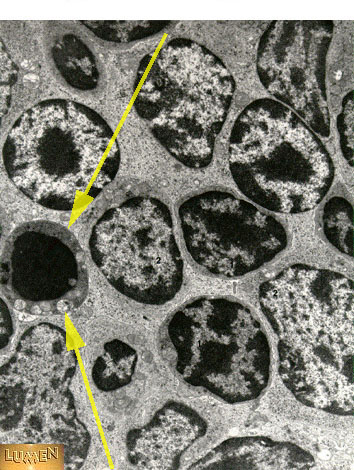

Thymocyte undergoing apoptosis